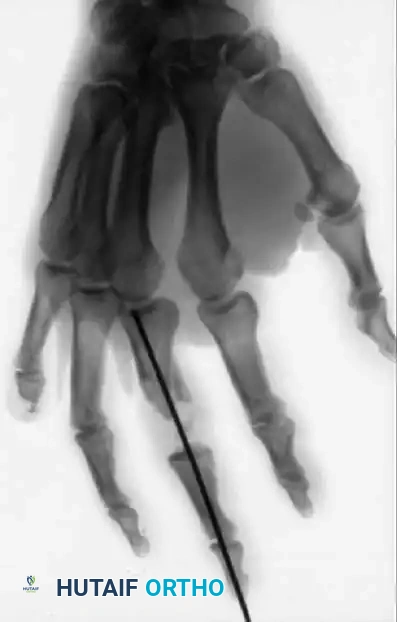

PRINCIPLES OF TREATMENT Surgical Diagram

Fig. 64-4 A and B, Open fractures of right hand with loss of distal end of middle phalanx and painful small fi nger partial amputation. C and D, Proximal phalanx of painful and stiff small fi nger was used as structural graft to restore articular column of middle fi nger.

Figure 64-4: Massive Trauma and Reconstructive Efforts.

A and B, Severe open fractures of the right hand demonstrating loss of the distal end of the middle phalanx and a painful, partially amputated small finger. C and D, Innovative reconstructive salvage: The proximal phalanx of the painful and stiff small finger was harvested and utilized as a structural bone graft to restore the articular column and length of the middle finger.